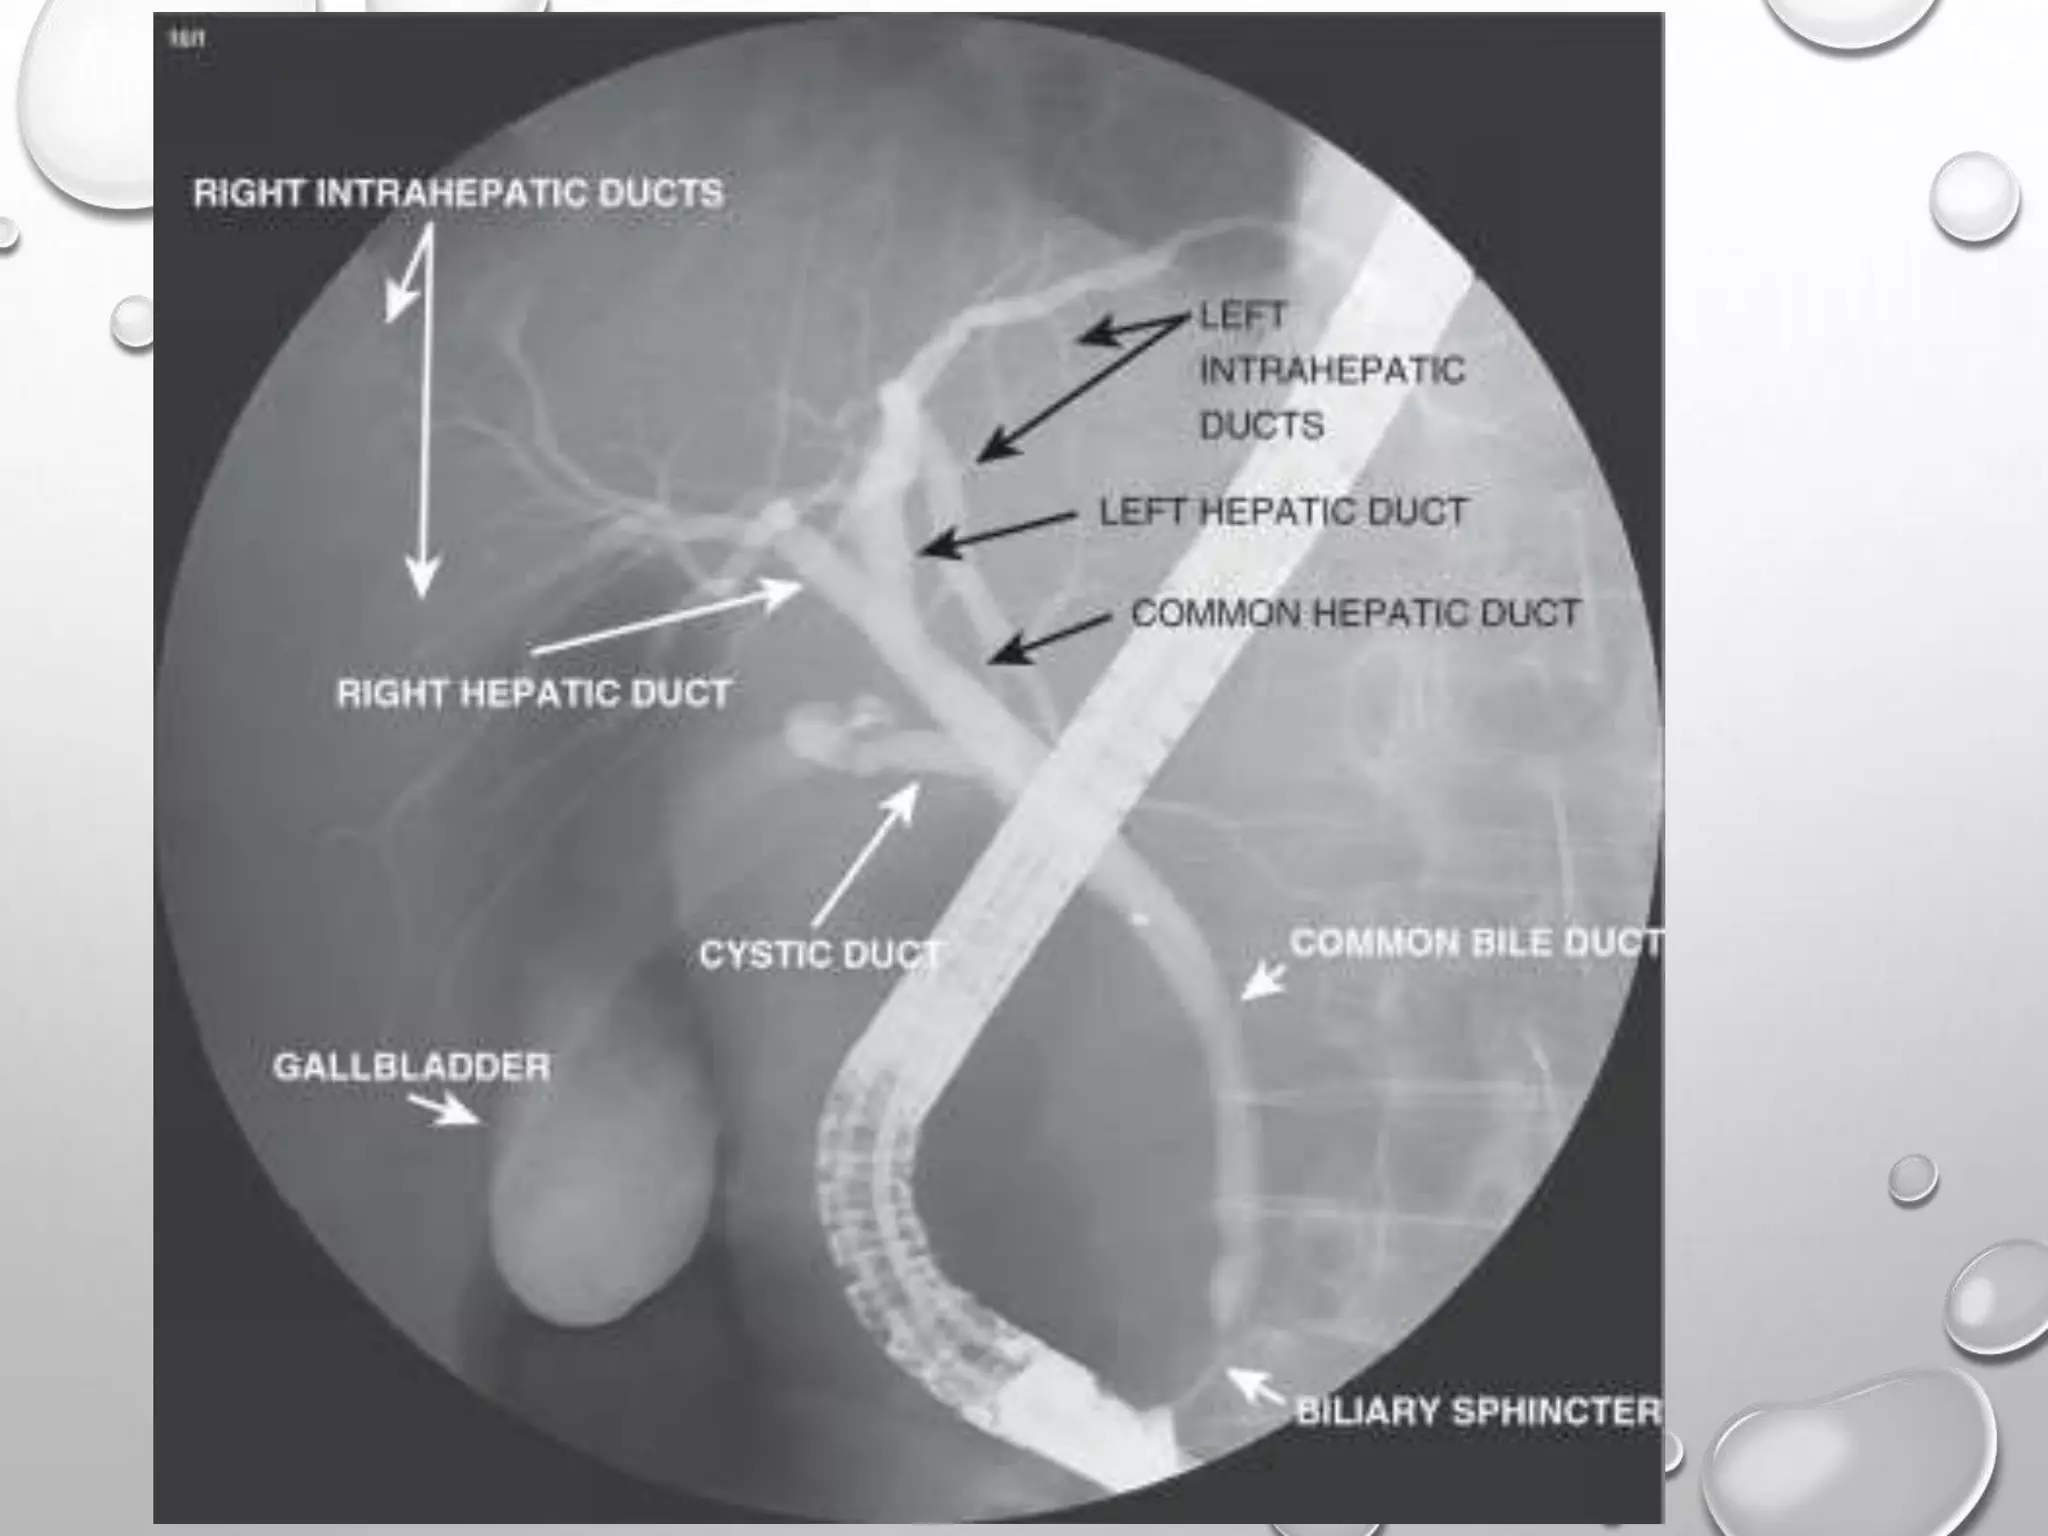

82-100% SENSITIVITY AND 94-98% SPECIFICITY

MRCP

It shows the abrupt termination of the dilated pancreatic and bile ducts at the level of the

pancreatic head, the classic sign of the presence of a carcinoma of the head of the pancreas.

82-100% SENSITIVITY AND94-98% SPECIFICITY MRCP

It shows theabrupt termination of the dilated pancreatic and bile ducts at the level of the pancreatic head, the classic sign of the presence of a carcinoma of the head of the pancreas.